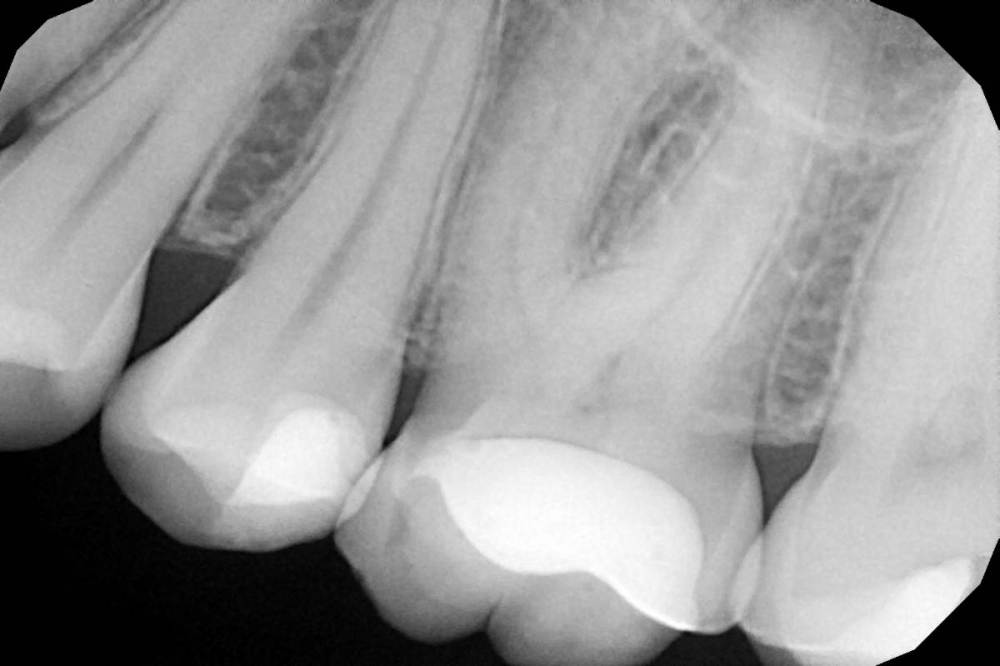

Женька Опубликовано 23 июня, 2021 Поделиться Опубликовано 23 июня, 2021 Коллеги, приветствую. Пришла пациентка с направлением на удаление 1.6-2.6 по ортодонтическим показаниям. Расспросив узнал, что принял решение такое ортодонт, тк премоляры интактны, а вот 1.6 эндодонтически пролечен. 2.6 с пломбой. Вопрос, оправдан ли такой подход? Есть лишь реконструкция КТ. Зубы я конечно не удалил, тк о таком подходе слышу впервые. Связавшись с ортодонтом узнал, что нестандартное удаление... Что думаете? p/s мудрые почему-то пока не удаляем... Ссылка на комментарий